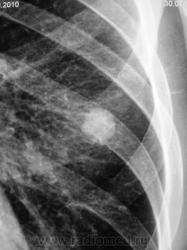

Томограммы.

Какая красивая "круглая тень"!

Ну, чем не периферический рак". А если присмотреться, так и контур полицикличен.

Или не рак?

Может и рак. А может и туберкулома. Есть снимки в динамике (за прошлые годы)?

А может гамартома...

Изображения с увеличением.

Похоже что это туберкулома. неоднородная структура?

округлое образование на фоне не изменённой легочной ткани - это гамартома

А, как насчет артерио-венозной аневризмы?

Аневризма? вряд ли...туберкулома 99%....

За 5 лет не выросло, значит добро, остальное сказать не возможно, патогномоничных симптомов гамартомы и туберкулромы, аневризмы нет

а-в мальформация?

Операция только и прояснит.

На операции - гамартома.